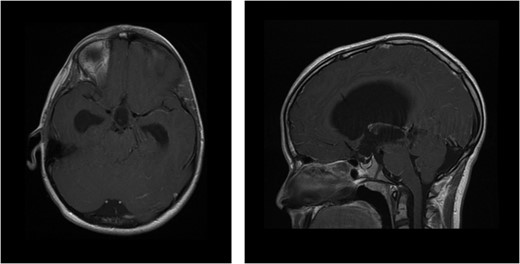

MRI of brain enhanced with contrast agent showing ventricular dilatation with aqueducts occlusion (axial and sagittal sequences, respectively).